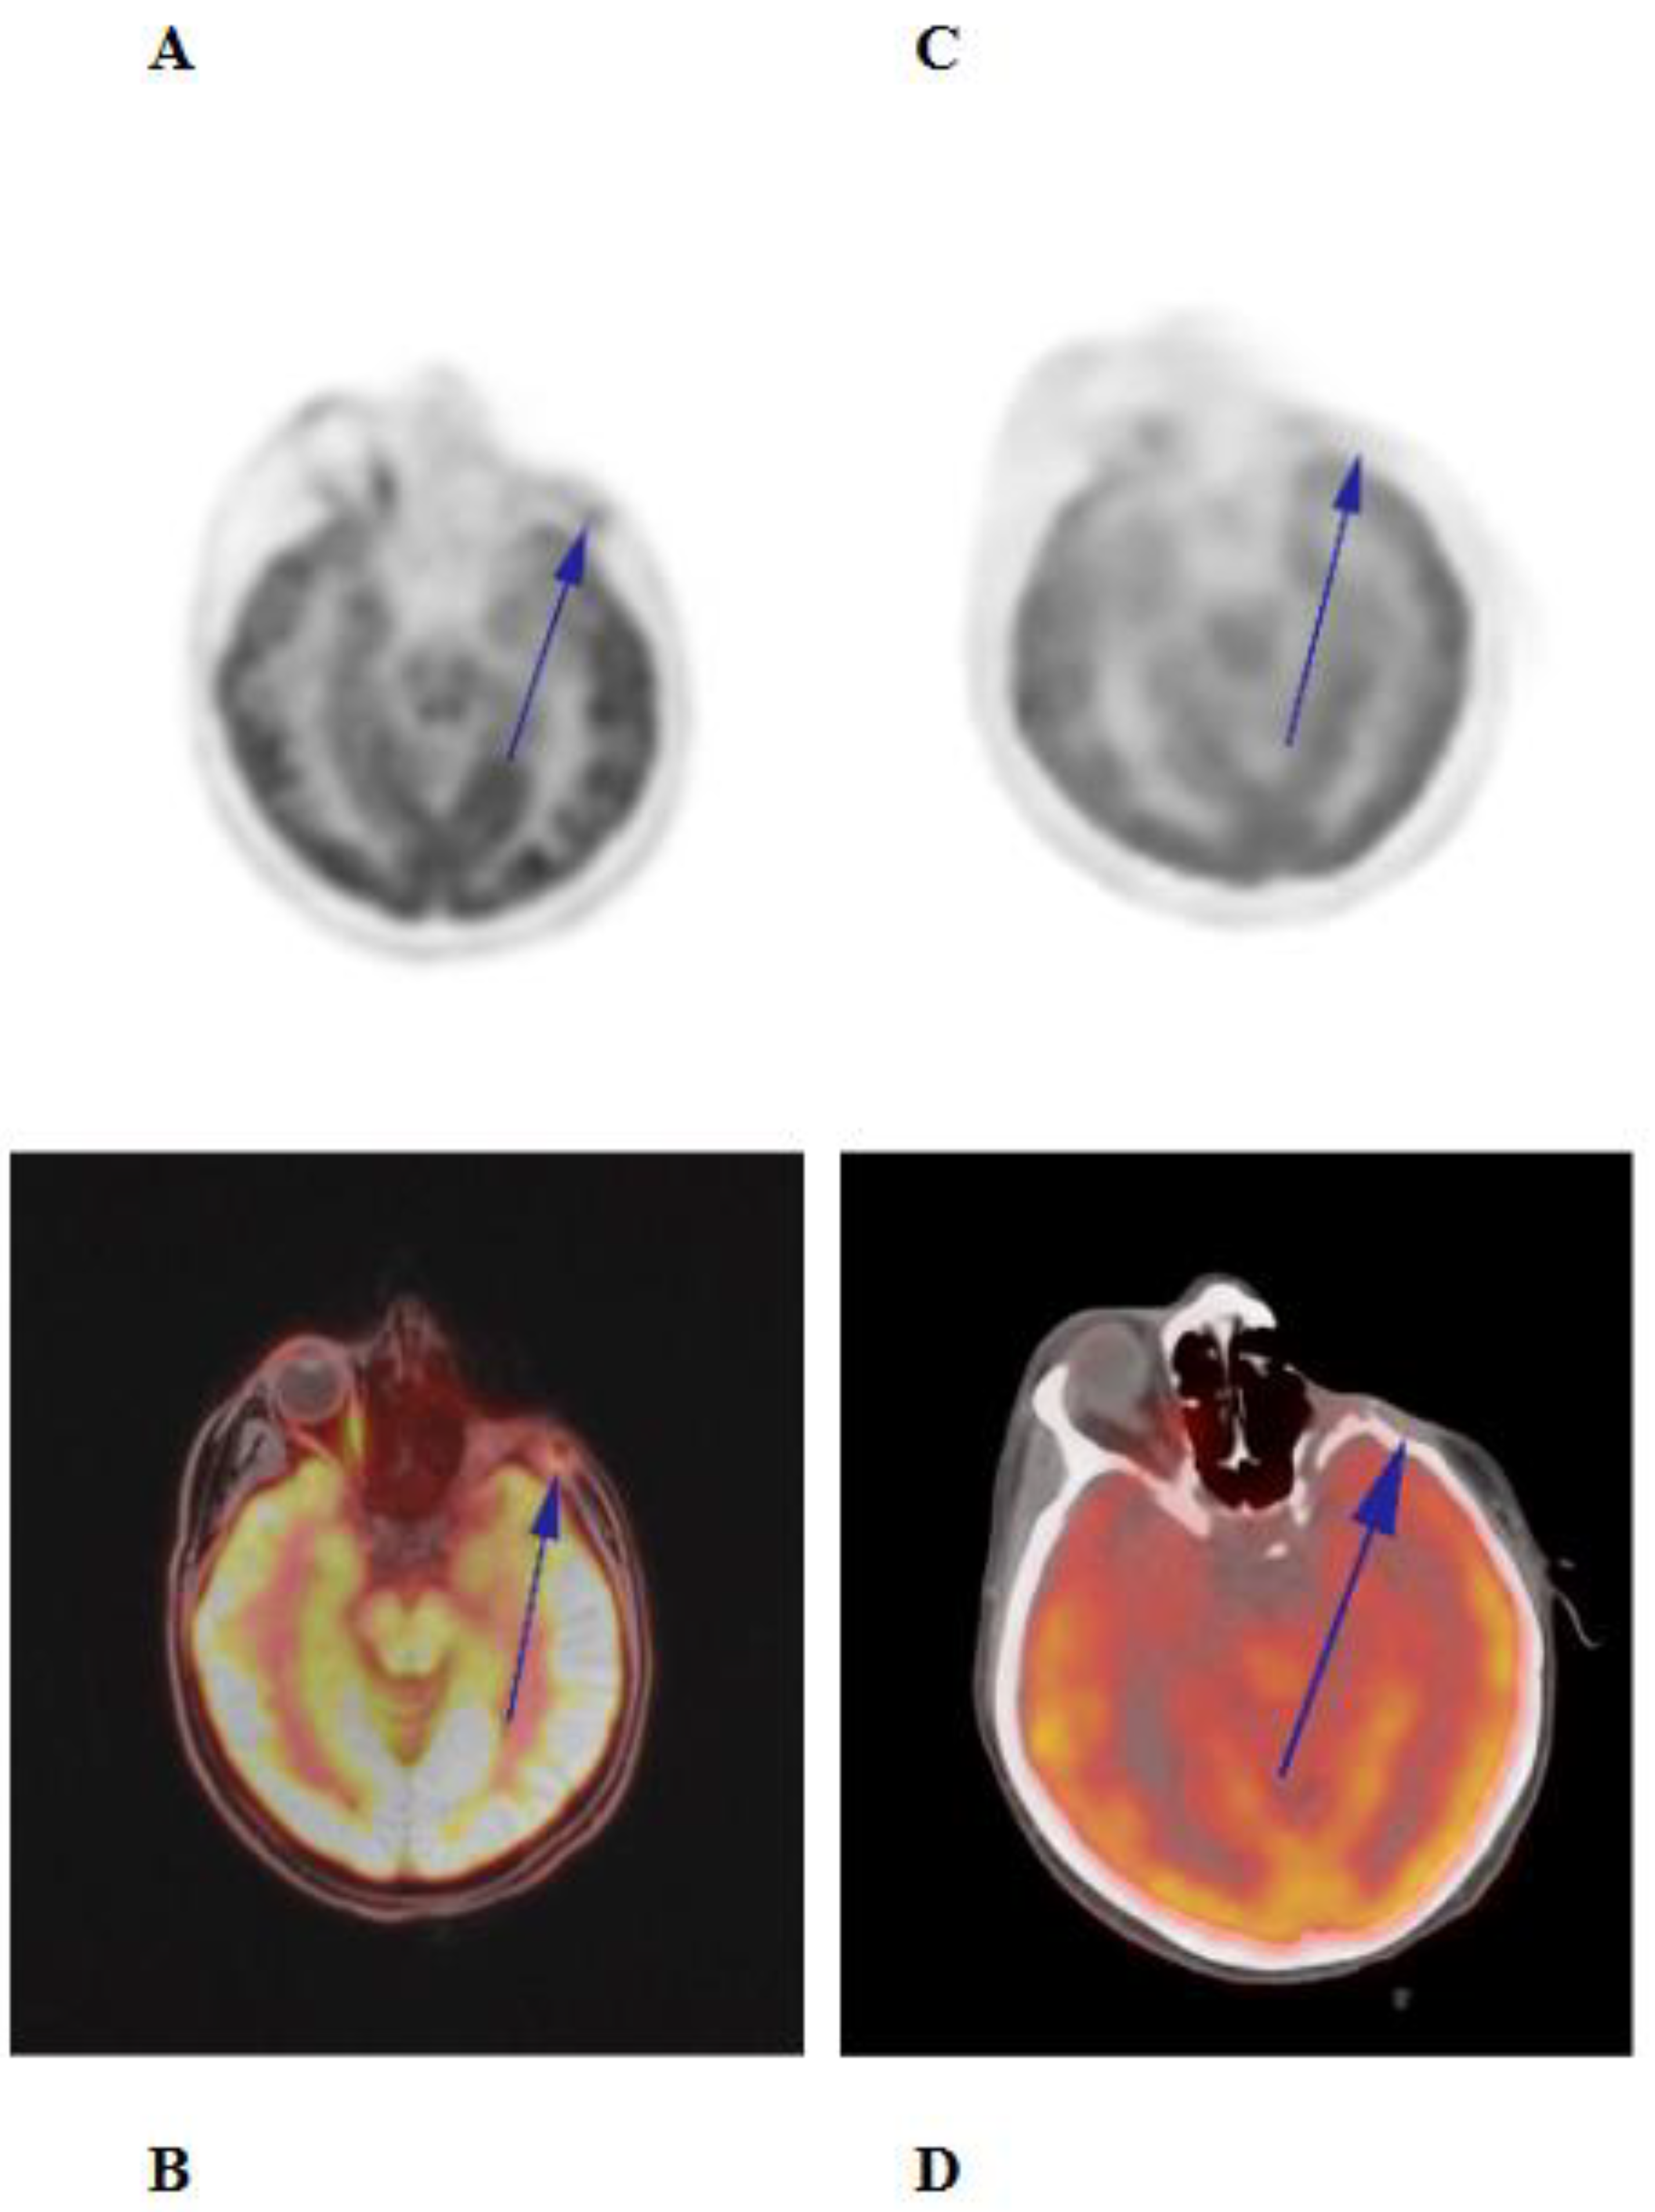

Case Presentation